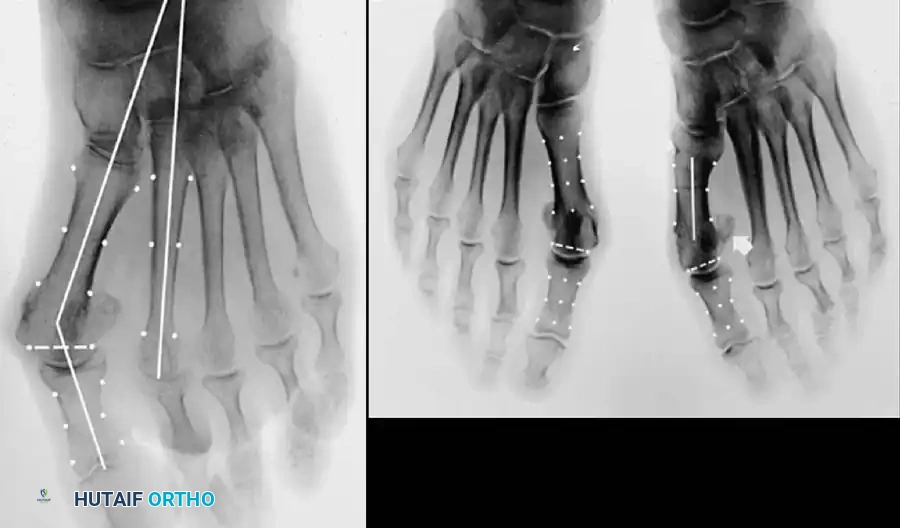

Inadequate vascularity or sensibility should be investigated thoroughly before bunion surgery is considered. In addition, the position of the articular surface of the metatarsal head in relation to the longitudinal axis of the fi rst metatarsal should be determined (Fig. 78-8). Standard preoperative radiographs should include standing dorsoplantar and lateral views, a nonstanding lateral oblique view, and axial sesamoid views (Fig. 78-9). The hallux valgus angle and the fi rst-second intermetatarsal angle should fi rst be drawn on the standing dorsoplantar view by bisecting the shafts of the bones (Fig. 78-10), with an awareness of the normal ranges. These angles are most frequently cited as guidelines for treatment decisions, but Donnelly et al. reported that interobserver measurements of the hallux valgus angle varied by approximately 6 degrees and of the intermetatarsal angle by 4 degrees. They cautioned that potential errors in measurement should be considered when these parameters are used to make treatment decisions. The hallux valgus interphalangeus angle and any evidence of degenerative arthritic changes at the fi rst metatarsophalangeal or metatarsocuneiform joints should be documented. Oddities may be present and, if overlooked, may compromise a technically well-done procedure. Mann emphasized that the presence of an os inter-

Fig. 78-8 A, Determination of position of articular surface of metatarsal head in relation to longitudinal axis of fi rst metatarsal. B, Measurement of distal metatarsal articular angle at time of surgery. Markings are at medial and lateral margins of articular surface of fi rst metatarsal head and longitudinal axis of fi rst metatarsal shaft. metatarseum between the bases of the fi rst and second metatarsals might preclude the effectiveness of a soft-tissue procedure alone to provide suffi cient correction of the increased intermetatarsal angle. Likewise, accessory sesamoids and prominent ungual tuberosities at the interphalangeal joint contribute to a painful callus at the tibial side of this joint. An os tibialis externum frequently is associated with excessive hallux valgus interphalangeus. Varus of the fi rst metatarsal might be a signifi cant part of the overall deformity of the foot even with an intermetatarsal angle of less than 10 degrees. Metatarsus varus with a relatively small hallux valgus angle (15 to 20 degrees) may produce signifi cant deformity even though the angles are not excessive. The usefulness of computer-assisted compared with manual measurement of the intermetatarsal angle, hallux valgus angle, and distal metatarsal articular angle is still uncertain. Both methods have closer interobserver and intraobserver correlation in measurement of the intermetatarsal angle and hallux valgus angle than in measurement of the distal metatarsal articular angle. The reliability of either method has such a wide range (5 degrees), however, that measurements of these angles, although useful as a guide, do not provide a completely reliable indication of the magnitude of deformity. Condon et al. suggested that the reliability of the intermetatarsal angle can be improved by careful technique and by making the measurements at least twice and averaging them. Schneider et al. reported two methods of determining angular measurements based on distinctly different reference points: (1) a longitudinal axis of the fi rst metatarsal using middiaphyseal reference points, and (2) a center-head technique using a center head (center of the articular surface) and center base

(center of the proximal diaphysis) as reference points. They found that measured correction of the hallux valgus and intermetatarsal angles varied by approximately 9 degrees depending on which reference points were used. Recommendations of Coughlin, Saltzman, and Nunley (American Orthopaedic Foot and Ankle Society Ad Hoc Committee on Angular Measurements) included standardized radiographic technique, specifi c placement of reference points (Fig. 78-11), use of a protractor rather than a goniometer for measurements, and, after distal osteotomies, dual measurements using a center-head technique and a Mose sphere.

Fig. 78-10 Method of measuring hallux valgus angle and intermetatarsal angle. Center points are connected, and intersecting lines defi ne angles.